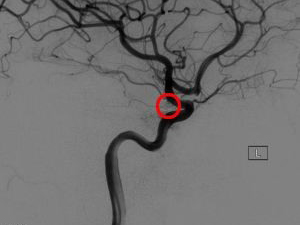

· 铂圈栓塞。这是一种比微血管外科夹闭更小的侵入性手术。医生会将一个空心塑料管(导管)插入动脉,通常在腹股沟,并将它穿过身体到脑动脉瘤。使用电线,医生将通过导管可拆线圈(微小的螺旋铂丝),并释放到动脉瘤。线圈阻塞动脉瘤,减少血液流入动脉瘤。这个手术可能需要在人的一生中进行不止一次,因为用弹簧圈治疗的动脉瘤有时会复发。